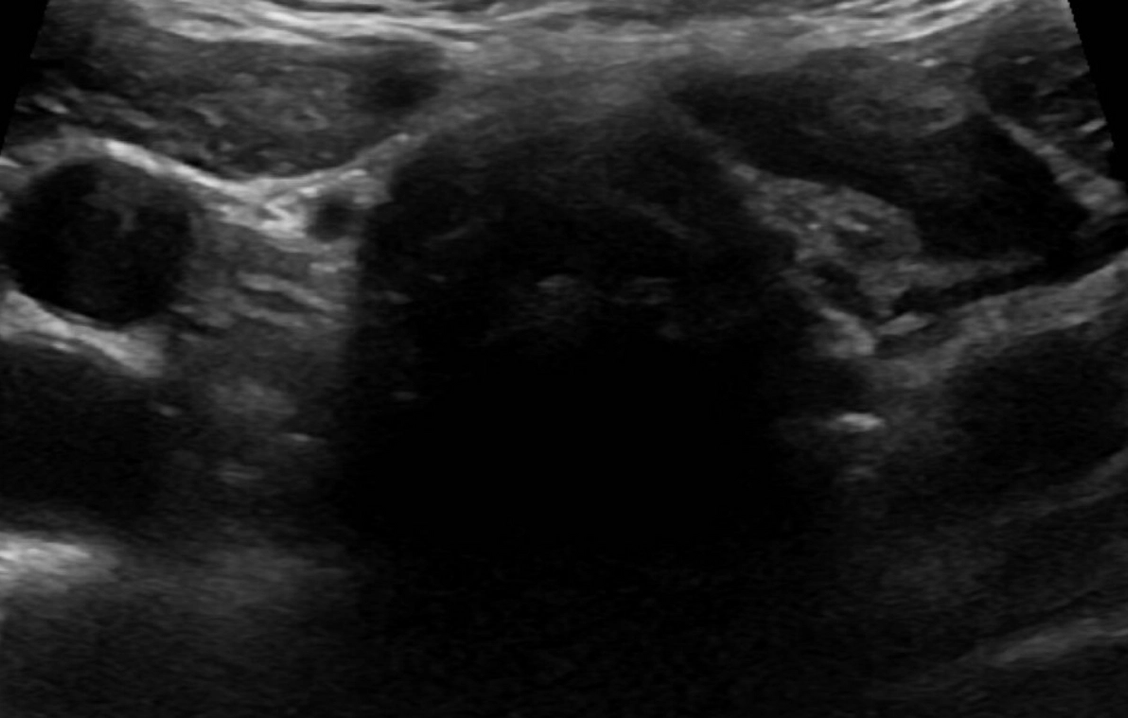

Your child’s thyroid is a small, butterfly-shaped gland in the front of the neck, just below the thyroid cartilage (Adam’s apple). Hormones produced by the thyroid affect all aspects of your child’s health including heart rate, energy metabolism (how effectively the body uses calories), growth and development.